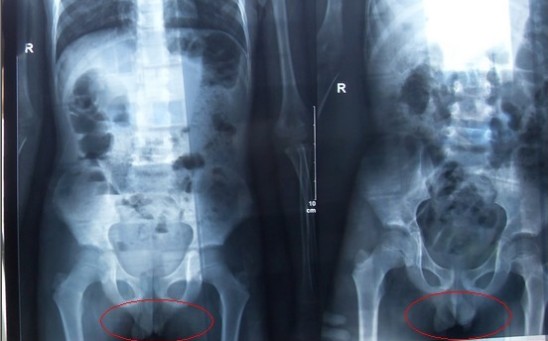

腹部立臥位X光片圖

2011年5月29日下午,陳先生的兒子安安出現嘔吐、肚子疼痛等癥狀。陳先生立即將兒子送往醫學院附院,根據醫生開出的會診單,分別對安安做了腹部立臥位2次和胸部正位1次共3次X光片檢查、診斷。醫生看X光片后排除了腸梗阻病因,判斷是闌尾炎。經過治療,不久安安身體痊愈。

可是,陳先生的一次偶然發現,讓他們一家過上了提心吊膽的日子。因為,在安安出院一個月后,陳先生偶然翻出孩子治療期間的X光片。發現在X光片中,孩子的生殖器官以及甲狀腺等敏感部位也在被放射區域中。而陳先生上網查到:人體拍攝X光片是有一定輻射的,并且輻射有可能引起基因變異等問題,他立馬陷入恐慌中。

至于,為什么拍攝X光時,孩子的敏感部位也在放射區域內,這讓陳先生百思不得其解。為此,他專門到醫學院進行了質疑。而醫院的醫務人員說,拍腹部X光片就要照到睪丸,要檢查睪丸是否正常,而且怕小孩亂動,所以要照寬些。